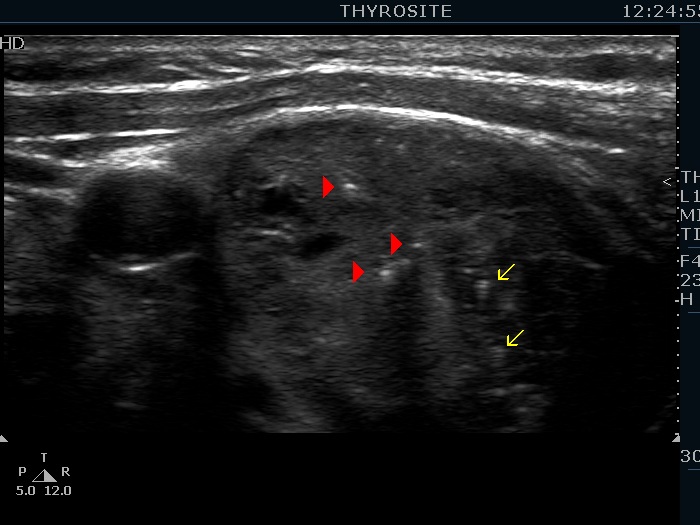

Intranodular hyperechogenic figures - case 876 (ultrasonographic picture 3b)

Right lobe, transverse view, enlargment. Note the presence of typical comet tail artifacts marked with yellow arrows and ambiguous granules marked with red arrowheads.